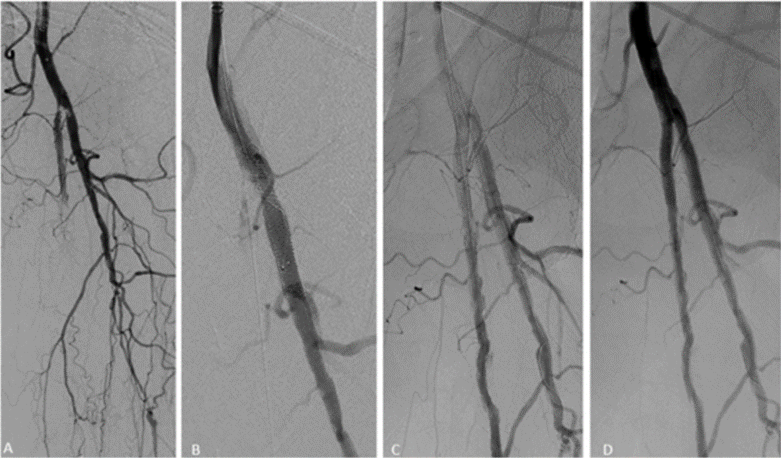

图2. 单支架,拘禁股浅动脉。患者为48岁女性,双下肢CLI,左侧膝上截肢,右足组织丢失。初始造影:左侧CFA严重狭窄,伴SFA近端和股深动脉多处狭窄(A)。左侧CFA血管成形术至5mm,股深动脉至4 mm。随后,从股深动脉至股总动脉植入5mm×80mm SUPERA支架(B),显影良好(C,D)

图片